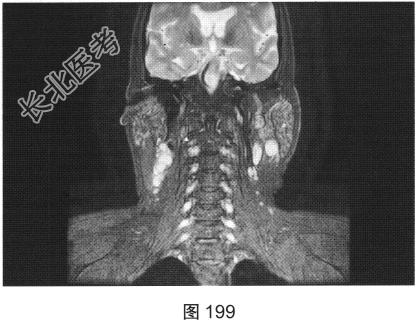

- 简答题2、患者行颈部平扫MRI检查,如图196~图199所示。请问患者MRI检查的阳性影像学表现有哪些?

- 简答题4、该患者行颈部淋巴结活检,组织病理学结合免疫组织化学染色,考虑非霍奇金淋巴瘤弥漫大B细胞型。对该患者进一步行胸部、腹部、盆腔增强CT检查,如图200、图201所示。请问患者以上CT检查可见哪些影像异常?